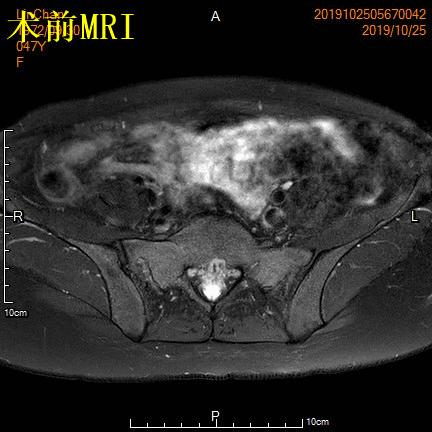

例1

青年女性患者,痛经近10年,近5年痛经明显加重。确诊为子宫腺肌症(弥漫型),经放置曼月乐、注射亮丙瑞林等妇科保守治疗,症状缓解不理想,痛经进行性加重,严重困扰工作与生活。

- 行子宫腺肌症介入栓塞治疗

- 术前MRI显示子宫明显增大,病灶主要位于子宫前壁

术前MRI显示子宫明显增大,病灶主要位于子宫前壁

术后3个月复查MRI显示子宫明显缩小,前壁病灶萎缩坏死